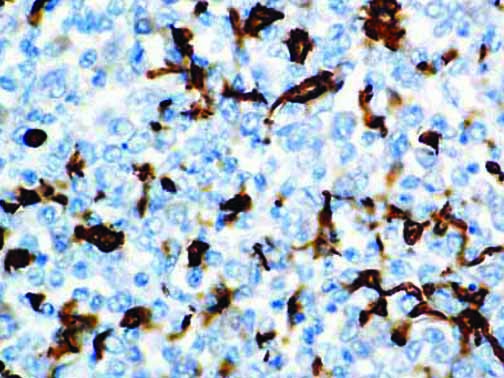

It is the ICU physician who is most likely to witness one of the deadliest manifestations of the abnormal immunological response, the cytokine storm syndrome (CSS). This response is also referred to by some as the cytokine release syndrome (CRS). CSS is characterized by continuous activation and expansion of macrophage and lymphocyte populations, which secrete large amounts of cytokines, causing the cytokine storm. This massive cytokine release is akin to hemophagocytic lymphohistiocytosis (HLH) disease, a syndrome characterized by initial unchecked and persistent activation of cytotoxic T lymphocytes and NK cells.

Clinical and laboratory manifestations of HLH include fever, enlarged liver and/or spleen, neurologic dysfunction, coagulopathy, liver dysfunction, cytopenias (i.e., low levels of erythrocytes, leukocytes, and/or platelets), hypertriglyceridemia, hyperferritinemia, hemophagocytosis, and eventually diminished NK cell activity as the immune system becomes progressively paralyzed. HLH can be familial (primary HLH) or secondary to another disease process (sHLH), such as rheumatic disease, in which it is referred to as macrophage activation syndrome (MAS, characterized by elevated ferritin).